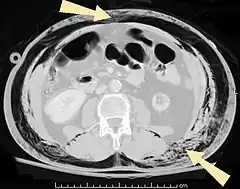

Pneumatosis is the abnormal presence of air or other gas within tissues.[1]

Pneumoperitoneum (or peritoneal emphysema) is air or gas in the abdominal cavity, and is most commonly caused by gastrointestinal perforation, often the result of surgery.